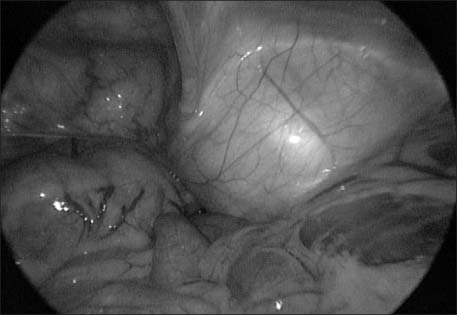

Fig. 2

Laparoscopic exploration showed well demarcated bulging mass from abdominal wall without connection of internal organ.

Fig. 2 Laparoscopic exploration showed well demarcated bulging mass from abdominal wall without connection of internal organ.

Fig. 3 Huge fatty mass encircled external iliac vein and femoral vein.